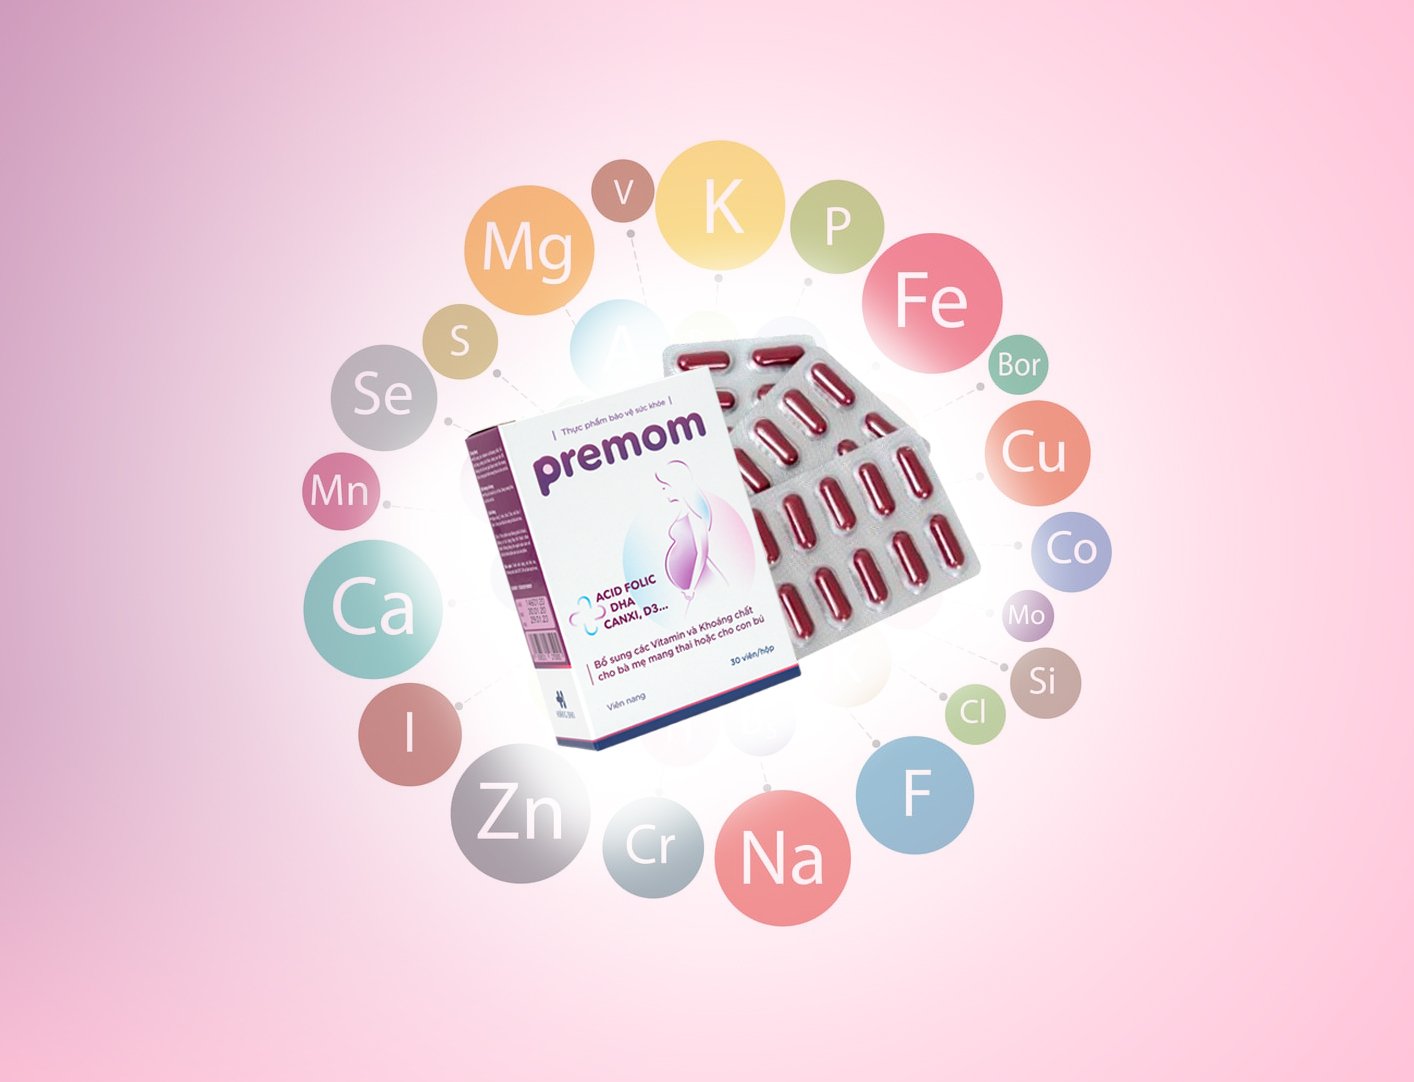

1. Cung cấp 22 vitamin và khoáng chất quan trọng nhất cho Mẹ bầu:

Sắt, Canxi, DHA, Folic Acid, D3, Kẽm, Vitamin A, … Toàn bộ được nhập khẩu từ các đối tác uy tín đến từ Mỹ và EU. Công thức được nghiên cứu theo khuyến nghị của Tổ chức Y tế Thế giới và phù hợp với đặc điểm sinh lý của phụ nữ Việt Nam.

Cơ chế tác dụng của các vitamin và khoáng chất trong vitamin giảm ốm nghén cho bà bầu Premom:

3. Bổ sung 22 vitamin và khoáng chất